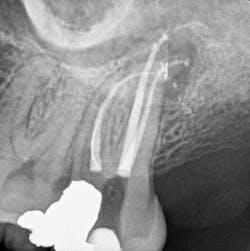

GT hand and rotary files took six years to develop. Conversely, within a month of conception, I had the first prototype electric heat plugger, and it worked well the first time I used it to do a Continuous Wave downpack. Ironically, in product development, it isn't always the failures that we must deconstruct and design around. With the CW Technique, it took more than two years to deconstruct that success to fully understand the power of "centered" condensation. Since then, I have been gratified to see the widespread adoption of this technique, making Schilder's filling results accessible to endodontists and general practitioners alike (figures 8a and 8b). To all who have adopted this technique, you have my deepest gratitude. But please, just a humble request, don't call it Vertical Condensation.

Figure 8a: Maxillary molar obturated with the Continuous Wave Technique. Note the significant lateral canal off the palatal canal. (Courtesy of Dr. Giuseppe Cantatore; Rome)

Figure 8b: Maxillary molar obturated with the Continuous Wave Technique. Note the multiple lateral canals and the long MB2 fin off the MB1 canal. (Courtesy of Constantinos Laghios, DDS, MS; Athens)